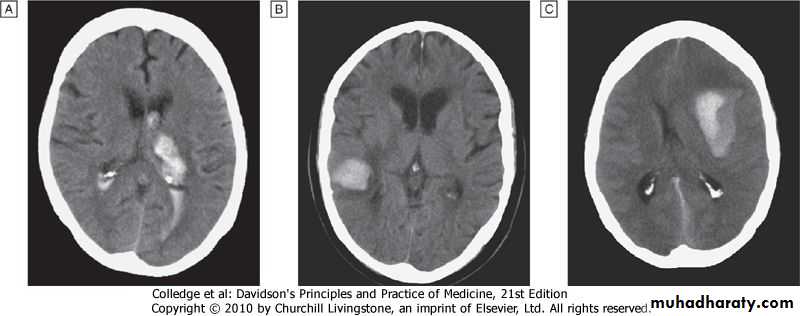

'Malignant' or 'accelerated' phase hypertension

RareAccelerated microvascular damage with

1-necrosis in walls of small arteries and arterioles ('fibrinoid necrosis') and

2- by intravascular thrombosis.

Diagnosis is based on

1- evidence of high blood pressure and

2-rapidly progressive end organ damage such as

retinopathy (grade 3 or 4),

renal dysfunction (especially proteinuria) and/or

hypertensive encephalopathy .

Left ventricular failure may occur and, if this is untreated, death occurs within months